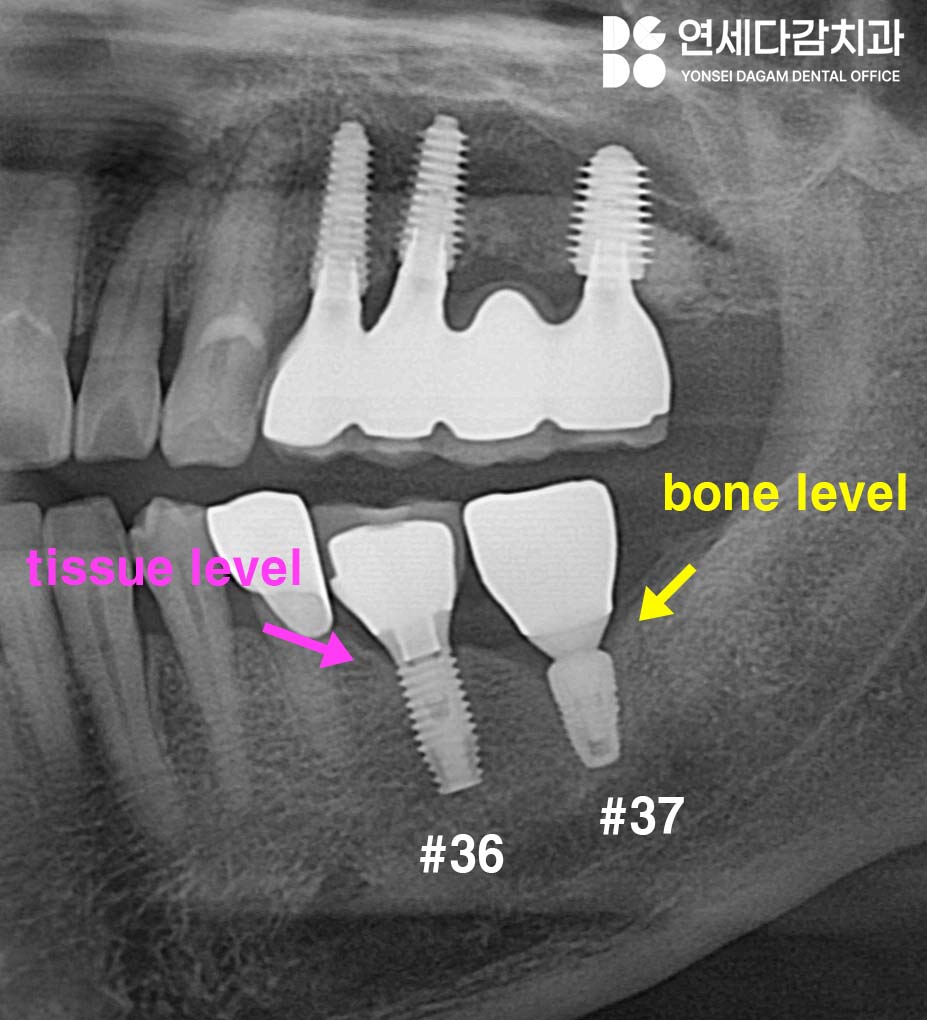

엑스레이 상 두 개의

종류가 다른 것을 알 수 있습니다.

개롱역 치과 에서

자세히 설명드리자면,

37번의 경우 요즘 많이 사용하는

internal hex type의

Bone level 타입이며,

36번 임플란트의 경우

tissue level 타입입니다.

이렇게 크게 Bone Level과

Tissue Level로

나눌 수 있습니다.

bone level은 고정체가

골 수준에 위치하도록 설계된 것이고,

tissue level은 잇몸 수준까지

올라와 있는 형태입니다.